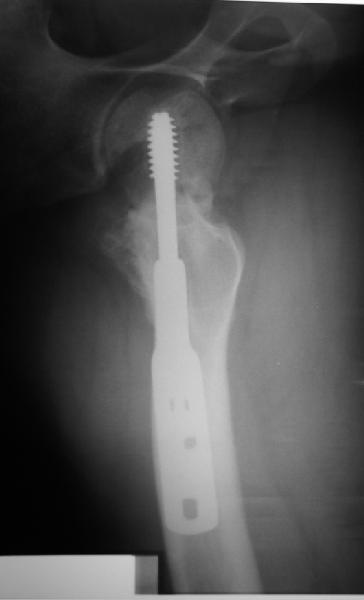

Несращение шейки бедра

Пациент 20 лет по поводу перелома шейки бедра оперирован в соседнем регионе 9 мес. назад.

На сегодня такая картина. Ходит с тростью, боли практически нет. Направили для эндопротезирования. У нас намерения больше в сторону вальгизируюещей остеотомии. То ли потом фиксировать как есть, то ли на уровне несращения шейки что-то подправить. Какие будут предложения?